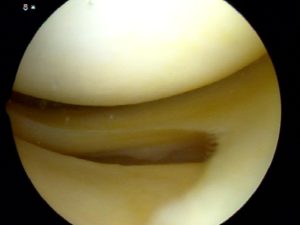

大家可以看到半月板已经完全有一部分离家出走,损伤肯定突破了其上下表面,并且导致了关节内的大量积液。而镜下很可能是这样子的:

而前角内见线性高信号影就说明为I-II°半月板损伤,因为损伤信号没有到达关节面,损伤是在半月板内部的,镜下很可能看见的是正常的半月板,下面是半月板II°损伤的核磁和镜下所见,和III°损伤有天壤之别。